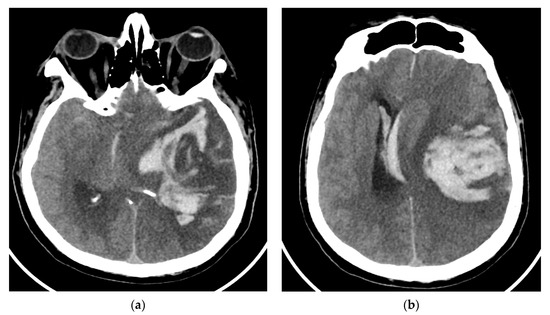

On day eight, the patient became comatose with altered neurological status and was intubated, with mechanical ventilation in the intensive care unit. He required i.v. fluids, pressors, ceftriaxone, vancomycin, and antifungals due to concerns regarding sepsis. A CT of the brain was obtained in light of the acute hemorrhage of intraparenchymal fronto-parieto-temporal lobes, showing important edema (Figure 4).

Figure 4.

(a,b), Brain-CT showed acute hemorrhage of intraparenchymal fronto-parieto-temporal lobes with important edema and ventricular extension.